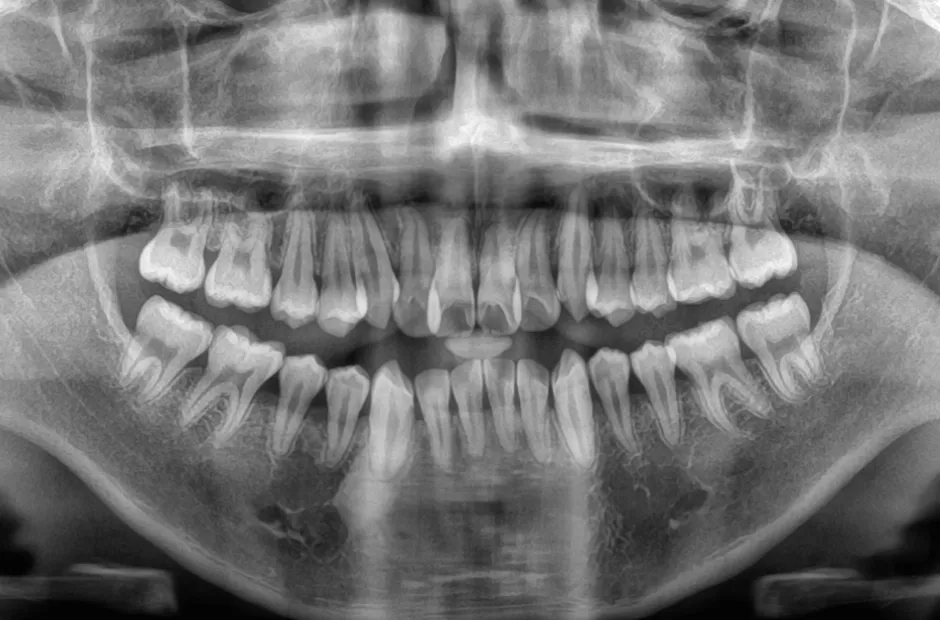

口腔内写真やレントゲンの撮影、歯型取りなど、口や顎の状態を詳しく把握するための精密検査を行ないます。さらに、骨の成長状況や身長・体重の増加傾向、永久歯の生えかわりについても確認します。

治療症例

前歯部反対咬合

| 診断名・主訴 | 前歯部反対咬合 |

|---|---|

| 年齢・性別 | 14歳・男性 |

| 治療期間・回数 | 1年2か月 |

| 治療に用いた主な装置 | ブラケット矯正 |

| 抜歯部位 | なし |

| 治療費 | 60万円(税抜) |

| リスク・副作用 | 装置による違和感・疼痛・歯肉退縮・歯根吸収・虫歯のリスクなど |

治療前